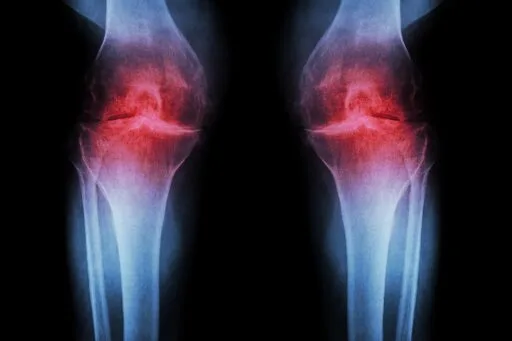

Anti-Aging Injection Regrows Knee Cartilage and Prevents Arthritis